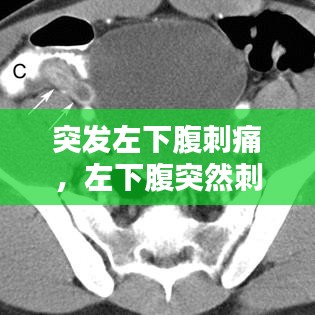

突发左下腹刺痛,左下腹突然刺痛的原因

什么是突发左下腹刺痛?突发左下腹刺痛是一种常见的腹部不适症状,通常指突然出现的、尖锐的、剧烈的疼痛,主要集中在左侧腹部下方。这种疼痛可能持续数秒到数小时不等,严重时可能会影响患者的日常生活。可能的原因突发左下腹...